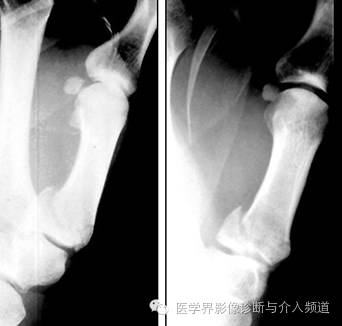

6、Colles 骨折

桡骨远端横形骨折。骨折线位于干骺端,邻近关节,远折端向背侧移位,断端向掌侧成角,通常伴尺骨茎突骨折。受伤机制为摔倒时候手撑地成过伸状。

7、Smith骨折

桡骨远端横形骨折,又称反Colles骨折。骨折线位于干骺端,邻近关节,远折端向掌侧移位,断端向背侧成角,通常伴茎突骨折。受伤机制摔倒时候手撑地呈过屈状。